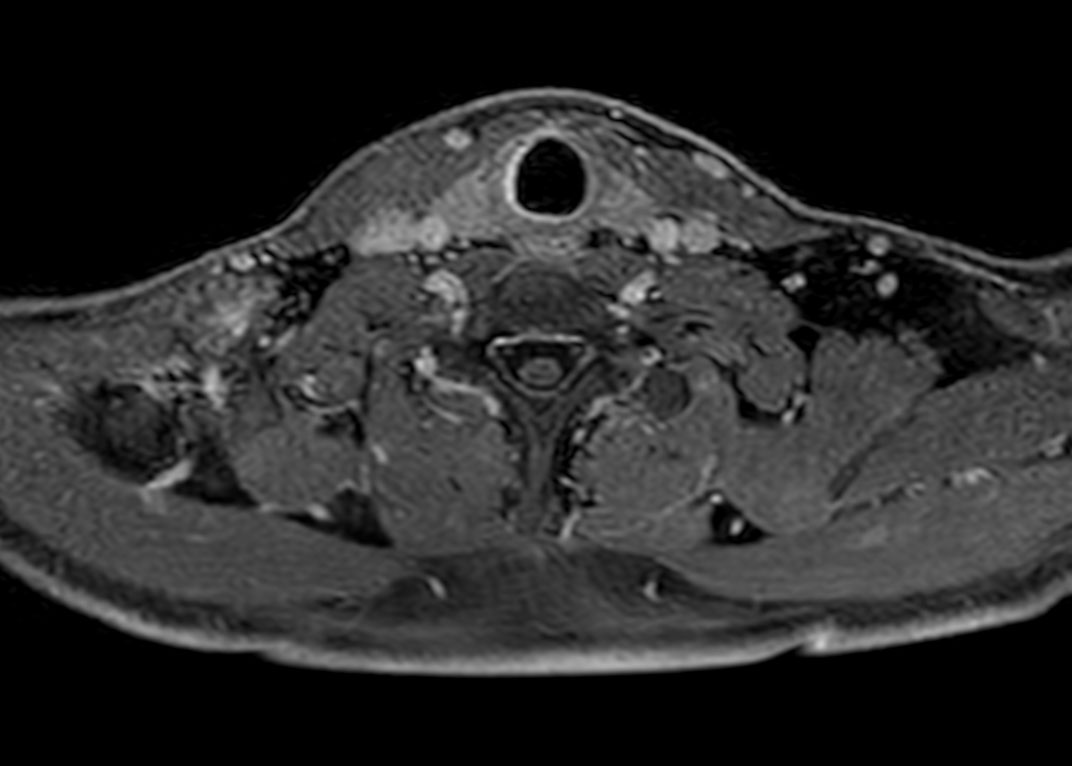

Axial T2w mDIXON XD TSE (In Phase)